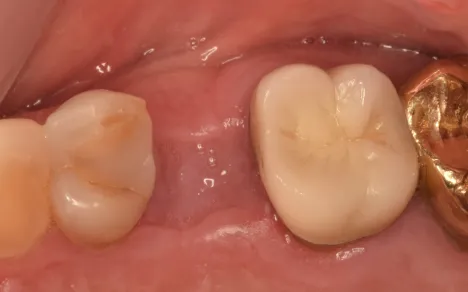

Dr.-Geivelis_Fig.4

Fig. 4. Socket preservation healing 3 months after surgery.